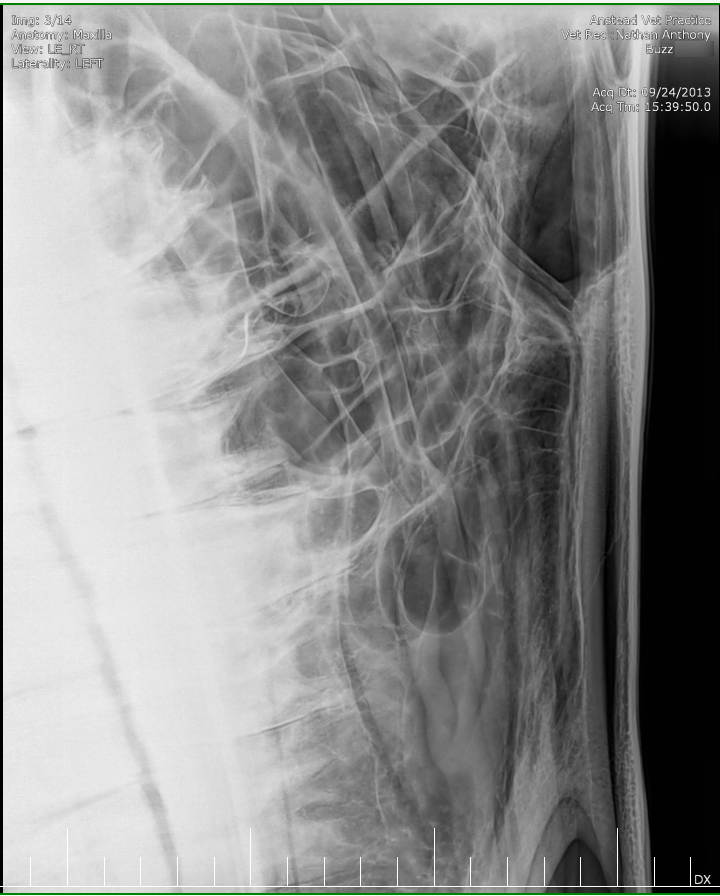

Posted on Sunday, May 8, 2016 - 6:24 pm: Thank you for the welcome!I did contact the lab to see if they still had the samples but they will only speak to the vets who submitted the samples. I've asked my vet to ask on my behalf but haven't yet heard back yet. The horse has been scoped and I was told that it all looked normal. The stylohoid bone and guttural pouches normal. The inflammation is mostly around the nostrils as per the pic but there are a couple of small spots further up inside the nose. He's also had his skull xrayed which I'm told also looked normal. I've included the pics at the bottom. I've included a list of other things here that have been tested to see if they influence the shaking or inflammation for the better or worse: - experimental course of Equity - Flixotide via inhaler - high dose of prednisolone - did work! - low dose of prednisolone - did not work - teeth checked by two different vet dentists - fly masks & nose nets - relocated him to several different places in the city incase it's an environmental allergen - all sorts of feed supplements - removed all hard feed, just feeding hay - stabled him 24/7 and fed him Haygain steamed hay incase it was something in the paddock - light/dark makes no difference to the shaking - it's not seasonal, happens year round I've also had bloodwork done and it showed a low red blood cell count. The blood was taken two weeks after the biopsies. My vet didn't think the low count was attributed to the blood loss from the biopsies so he suggested parasites but a worm count came back clean. I also had a test to see if there was blood in the manure, but nothing was found. There was no plan made to address the low RBC. Results are attached in a text file to maintain the spacing.

Xray images: